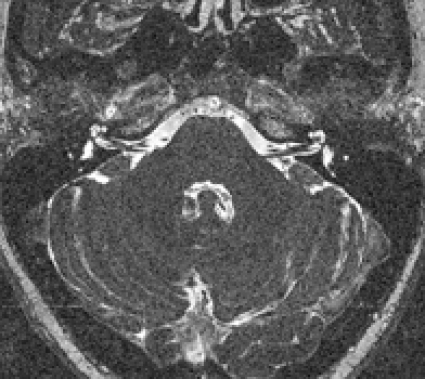

Morfologiska bilder med hög upplösning. Morfologisk MR med hög upplösning är värdefull, tex för undersökning av temporalben och kranialnerver (Figur 1). Tredimensionell T1-viktad gradientekosekvens kan erhållas med hög isotropisk upplösning. Den används tex för att detektera migrationsstörningar hos barn med epilepsi och som morfologiskt bildunderlag för överlagring av fMRI-data.